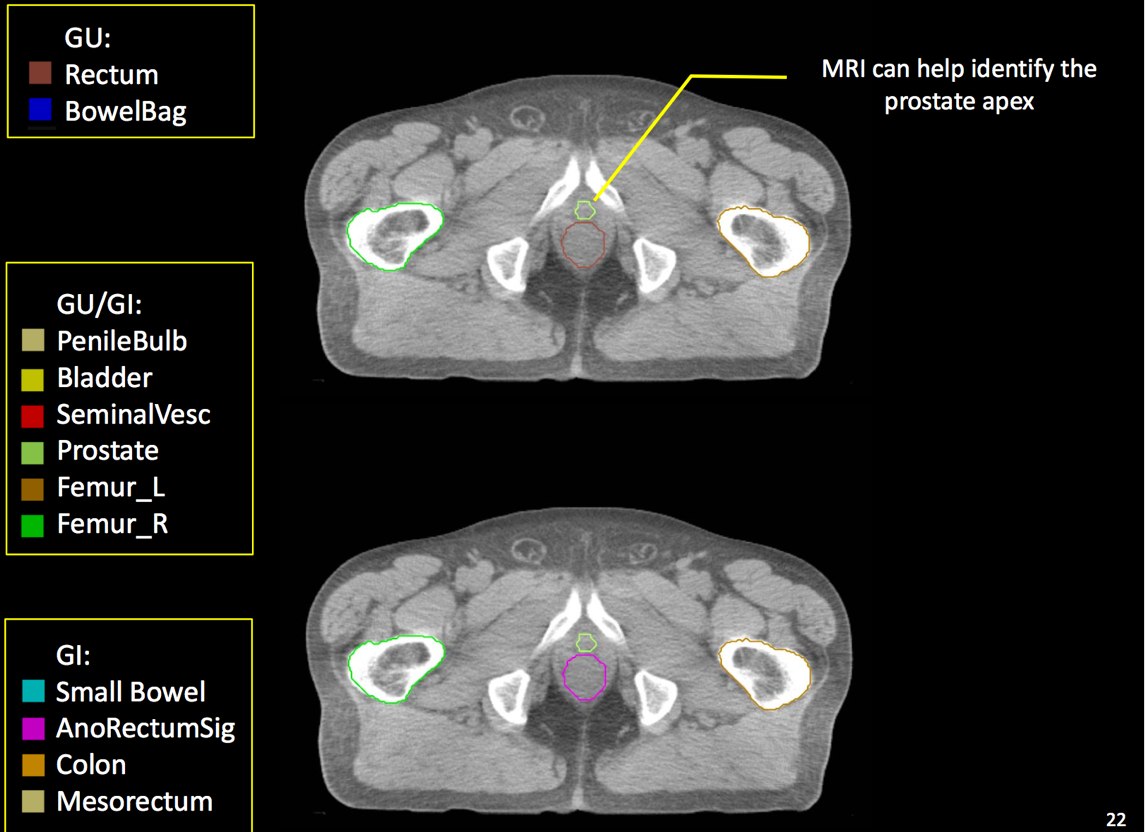

At a minimum, the following contours should be available to the planners:

• prostate

• seminal vesicles (treat at least proximal if risk calculated > 15% --ucsf)

• pelvic lymphatics (if treatment indicated -- risk > 15% -- ucsf)

• femoral heads

• rectum

• bladder

• bowel (where necessary due to bowel prolapsing below the bladder)

• penile bulb

The target volume (CTV) is defined as the prostate and seminal vesicles. The planning target volume expands the CTV to take into account setup uncertainties, both systematic and physiologic. By using daily image guidance, where available, physiologic parameters are more controlled and allow the reduction of CTV expansion required to fully cover the prostate and adjacent tissue at risk.

There is significant variation of contours and techniques. The apex and base are regions most susceptable to variation. 3D perspectives help signficantly reduce this variation using transverse, sagital and coronal projections to determine the true extent of the prostate. More recently contouring atlases have been developed by the RTOG with grant assistance from the NCI and are available here. The following images are obtained from the RTOG contour atlases as an excerpt demonstrating areas of potential uncertainty.

There are recent efforts to standardize segmentation names for radiotherapy treatment planning. This is encouraged to allow for inter-institution comparisons, particularly on protocol patients, but it may also assist institutions in comparing dosimetry should additional radiotherapy or other dose questions arise. The normal clinical structures to be identified are: